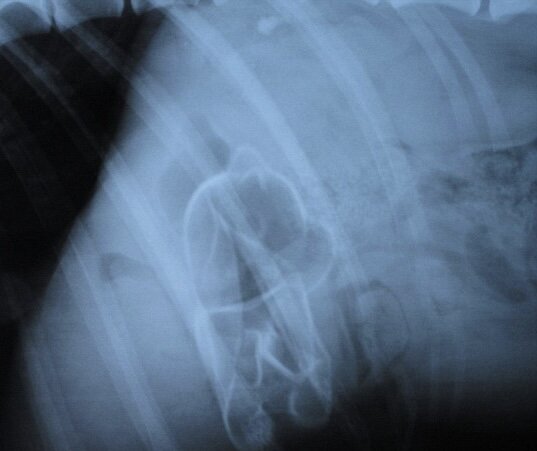

Рассказали историю, что недавно к ним попал пёс на приём, которого тошнило неделю, при этом аппетит не пропал и бегал он как молодой олень. При прощупывании живот был мягкий, лечение таблетками не помогло и только тогда начали делать анализы. Рентген ничего не показал, а вот на УЗИ определили, что в полости живота застряла палка около 25 сантиметров. Каким-то образом лабрадор заглотил её и она вызывала у него рвотный рефлекс. Эта история меня не очень подбодрила, но впечатлила.

Резиновая игрушка в животе у лабрадора. Фотография из открытого источника.